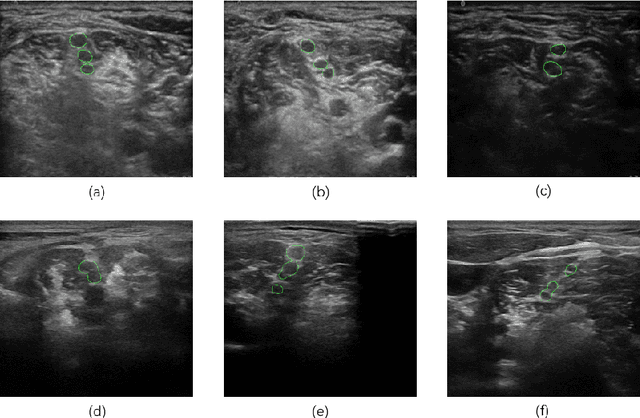

Abstract:Ultrasound-guided nerve block anesthesia (UGNB) is a high-tech visual nerve block anesthesia method that can observe the target nerve and its surrounding structures, the puncture needle's advancement, and local anesthetics spread in real-time. The key in UGNB is nerve identification. With the help of deep learning methods, the automatic identification or segmentation of nerves can be realized, assisting doctors in completing nerve block anesthesia accurately and efficiently. Here, we establish a public dataset containing 320 ultrasound images of brachial plexus (BP). Three experienced doctors jointly produce the BP segmentation ground truth and label brachial plexus trunks. We design a brachial plexus segmentation system (BPSegSys) based on deep learning. BPSegSys achieves experienced-doctor-level nerve identification performance in various experiments. We evaluate BPSegSys' performance in terms of intersection-over-union (IoU), a commonly used performance measure for segmentation experiments. Considering three dataset groups in our established public dataset, the IoU of BPSegSys are 0.5238, 0.4715, and 0.5029, respectively, which exceed the IoU 0.5205, 0.4704, and 0.4979 of experienced doctors. In addition, we show that BPSegSys can help doctors identify brachial plexus trunks more accurately, with IoU improvement up to 27%, which has significant clinical application value.